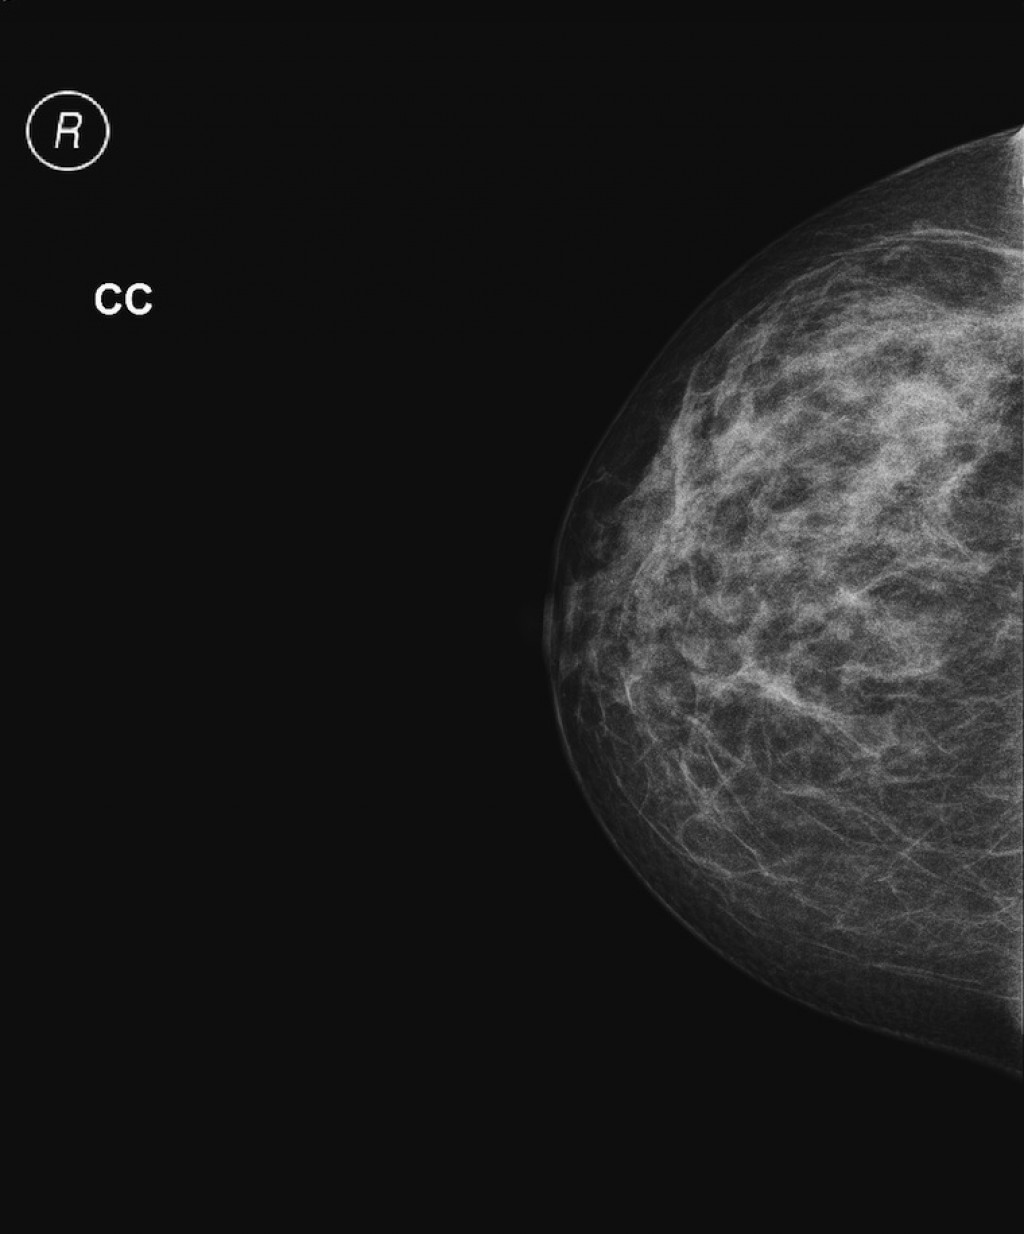

Фиброаденома молочной железы - доброкачественное образование, которое часто встречается у женщин. Оно может быть обнаружено при помощи различных методов диагностики, включая маммографию. Ниже представлены фотографии, помогающие понять, как выглядит данное заболевание.

Маммограмма железистая ткань

Маммография и ее роль в диагностике фиброаденомы молочной железы

Маммография - это рентгенологическое исследование молочных желез. Оно позволяет выявить различные изменения в тканях, включая фиброаденому. На маммограммах можно увидеть структурные особенности опухоли и отследить ее динамику во времени.